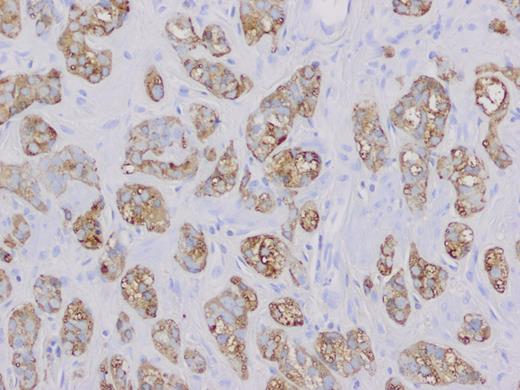

A 58-year-old Caucasian female presented with episodic right upper quadrant pain for the past 2 weeks. The pain was associated with multiple episodes of nausea, vomiting and diarrhea. She denied any jaundice, weight loss, hematochezia or melena. Physical examination revealed a soft abdomen without a palpable mass. She had tenderness in the right upper quadrant of the abdomen and Murphy's sign was present. The white blood cell count was 18.8K/µl, hematocrit 41.0%, bilirubin 0.20 mg/dl, lipase 101 U/l, alkaline phosphatase 70 U/l, alanine aminotransferase 28 U/l and aspartate aminotransferase 30 U/l. Computed tomography of the abdomen showed an enlarged fatty liver, mildly prominent gallbladder and inflammatory changes and edema at the root of the mesentery. Abdominal ultrasound revealed gallbladder sludge and wall thickness measuring 2 mm. The patient underwent laparoscopic cholecystectomy. Pathology report revealed mild chronic cholecystitis with foci of cholesterolosis and a small 2 mm carcinoid tumor at the cystic duct margin extending into the gallbladder mucosa. Histologically, the tumor demonstrated uniform eosinophilic neoplastic cells with oval nucleus (Fig. 1) and was positive for chromogranin and synaptophysin neuroendocrine markers (Figs 2 and 3).